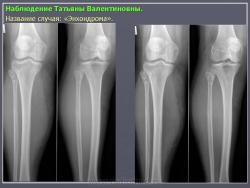

Энхондрома (син.: хондрома, центральная хондрома) — доброкачественная хрящевая опухоль, расположенная в костномозговом канале (интрамедуллярно). Встречается в 10 % случаев от общего числа доброкачественных опухолей костей. Считается, что она возникает из эктопически расположенных островков хряща, отщепившегося от пластинки роста на ранних этапах онтогенеза. В ряде случаев опухоль остается бессимптомной и обнаруживается случайно при рентгенологическом исследовании. В других случаях возникают боль и припухлость. Обычно болезненными становятся все энхондромы фаланг. Наиболее частая локализация: фаланги, главным образом, пальцев кистей, проксимальный конец плечевой кости, проксимальный или дистальный концы бедренной кости. При рентгенологическом исследовании в энхондроме определяются просветления с участками минерализации. Тень кости становится более широкой, кортикальный слой сохраняет целостность, но истончается. В редких случаях энхондрома имеет вид эксцентрически растущего экзофитного новообразования. Макроскопически опухоль представляет собой голубовато-белую полупрозрачную хрящевую ткань, в которую вкраплены желтоватые участки обызвествления. Опухоль состоит из отдельных хрящевых узелков, диаметр которых варьирует в пределах 1 см.

Энхондроматоз (син, болезнь Оллье) — редкая врожденная патология, не передающаяся по наследству, при которой у больных имеется множество доброкачественных хрящевых опухолей, главным образом на конечностях. Пораженная конечность укорачивается и деформируется. После завершения полового созревания заболевание не прогрессирует. Возможна малигнизация, которая отмечается в возрастном промежутке 13—69 лет. Локализация: энхондромы обнаруживаются в метафизах, диафизах, эпифизарных пластинках и суставных хрящах. Это интракортикальные и/или периостальные поражения в виде отдельных опухолей, не сливающихся друг с другом. Им присущ основной признак энхондроматоза — богатство клетками (гипериеллюлярность), причем встречается много двуядерных хондроцитов. И гиперцеллюлярность, и цитологическая атипия при энхондроматозе выражены значительнее, чем при солитарной энхондроме.